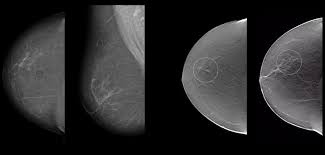

El diagnóstico mamario es una herramienta fundamental para el cuidado de la salud de la mujer. A través de estudios de imagen mamaria como la mastografía, el ultrasonido de mama y la resonancia magnética mamaria, es posible detectar de forma temprana cualquier cambio o lesión en el tejido mamario, incluyendo el cáncer de mama, la enfermedad más frecuente entre las mujeres a nivel mundial.

Detección temprana del cáncer de mama

Permite identificar lesiones o tumores en etapas iniciales, incluso antes de que sean palpables. Un diagnóstico oportuno aumenta las probabilidades de tratamiento exitoso y supervivencia.

Evaluación precisa del tejido mamario

Mediante estudios como la mastografía, ultrasonido o resonancia mamaria, se logra una visualización detallada del tejido, diferenciando entre cambios benignos y lesiones sospechosas. Esto evita diagnósticos erróneos y tratamientos innecesarios.